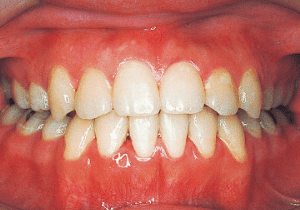

2 After treatment 2-10-’99

22 After treatment 2-10-’99 17 years 7 month

23 After Retention 1-22-’01 19 years 6 month

Although early treatment improved the slight deviation observed during the deciduous dentition stage, it became apparent that the deviation increased with age, eventually exceeding the limits of treatment. This appears to be an innate deviation, and the developmental pattern observed in this case seems to disregard the occlusion. Four first premolars were extracted (15), crowding was corrected and space closure was performed (16), and surgical intervention improved the deviation (17).